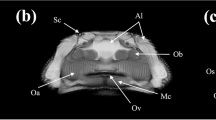

Phosphomolybdic acid-stained functional spinal units (FSUs) revealed increased attenuation of the notochordal tissues across all samples (Fig. 1). The Intraclass correlation coefficient (ICC) confirmed that the contouring and segmentation for the disc was reproducible (Table 1). The microCT-1µm and microCT-6 µm-derived IVD compartment volumes were statistically indistinguishable (paired t-test, p = 0.99) and highly correlated (Pearson’s correlation, p < 0.001, r2 = 0.99), suggesting that scanning at 6 µm spatial resolution is a reasonable compromise to measure the notochord volume (Fig. 2; Figure S1). Examination of the correlations in the individual AF, NP, and NC compartments show that although while the 1µm- and 6 µm- microCT data were highly correlated for the AF (Pearson’s correlation, p < 0.001, r2 = 0.87) and the NP compartments (Pearson’s correlation, p < 0.01, r2 = 0.89), the NC compartment correlation resulted in significant, but less correlated values (Pearson’s correlation, p < 0.05, r2 = 0.67), suggesting that there are trade-offs in accuracy in the 6 µm-resolution scans. An examination of the grayscale transverse sections confirms that the images obtained at the 1 µm resolution reveals more detail particularly of the notochord and the collagen-rich extra-cellular matrix (Fig. 1).

Grayscale images of transverse sections from murine intervertebral discs across different ages. The darker shades reflect lowly attenuating regions and, and the lighter shades reflect highly attenuating regions. The blue dashed line outlines the annulus fibrosus (AF) region, the red dashed line outlines the nucleus pulposus (NP) region, and the green arrows indicate the notochordal (NC) remnants. The notochord structure is highly attenuating from the PMA chelation of the collagen residues. The AF and NC tissues attenuate higher than the NP, allowing for segmentation of three distinct compartments. At early timepoints, the NC is a nondiscrete structure that spans across a large area of the NP. With age, the NC becomes more discrete within the middle of the NP and grows in size.